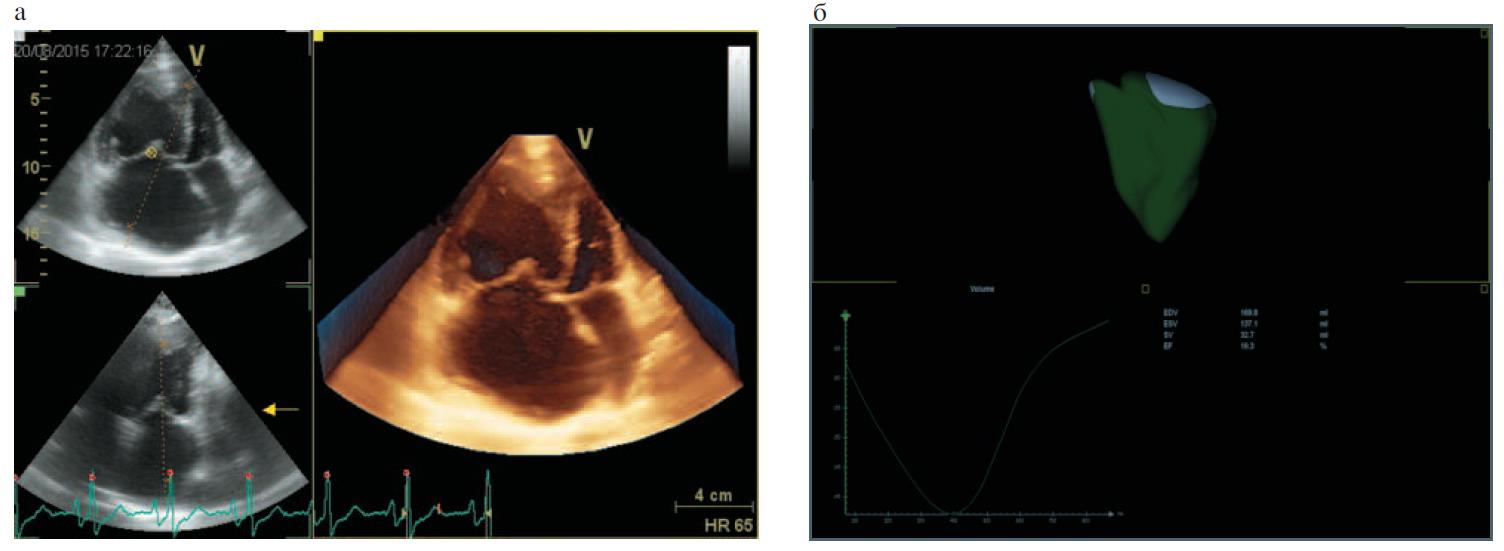

С помощью метода 3D-ЭхоКГ проводилась оценка объемных показателей и ФВ ПЖ у 26 пациентов, из них у 9 – с ИЛГ, у 8 – с ГБ, у 9 – с ХСН, а также у 8 практически здоровых лиц (КГ); табл. 2. Пример расчета объемов и ФВ ПЖ по данным 3D-ЭхоКГ представлен на рис. 1. Сопоставление с данными МРТ выполнено у всех лиц, которым проводилась 3D-ЭхоКГ. При оценке систолической функции ПЖ как по данным 3D-ЭхоКГ, так и по данным МРТ минимальные значения ФВ ПЖ также выявлены в группах ИЛГ и ХСН, которые достоверно отличались как от КГ, так и от группы ГБ. Во 2-й группе средние значения ФВ ПЖ не выходили за пределы референсных значений, несмотря на достоверные отличия по сравнению с КГ (см. табл. 2).

Рис. 1. Пример расчета объемов и ФВ ПЖ по данным 3D-ЭхоКГ у пациентки с ИЛГ: а – апикальная 4-камерная позиция; б – трехмерная модель ПЖ.